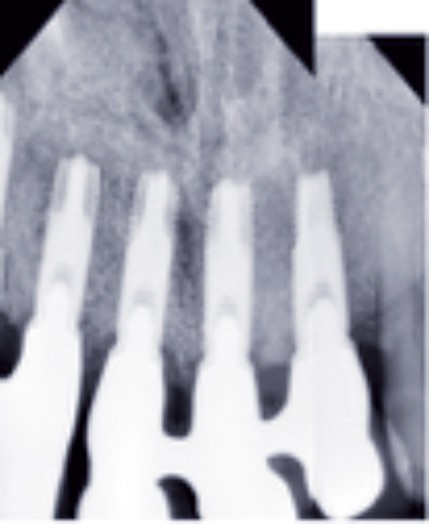

Cette partie de la présentation ne se contentait pas de rapporter les principes précédemment décrits à des régions limitées des maxillaires mais étendait la discussion à la difficulté majeure rencontrée en implantologie : rattraper des erreurs de positionnement implantaire ayant entraîné des compromis prothétiques inesthétiques. La solution thérapeutique mise en œuvre par Benoît Philippe consiste à appliquer la procédure d’ostéotomie segmentaire à l’entité constituée par l’os alvéolaire péri-implantaire et les implants. Les couronnes implantaires sont déposées. Le tracé d’ostéotomie encadre le segment à repositionner mais n’implique pas la corticale palatine qui sera fracturée pour éviter toute lésion du périoste (nourricier du segment alvéolo-implantaire). Un dispositif prothétique préparé en amont guide la translation du fragment qui est fixé au moyen de plaque d’ostéosynthèse dans la situation idéale. Le capital squelettique est reconstruit et l’espace prothétique disponible est normalisé.

La procédure chirurgicale du cas est à visionner sur : www.idweblogs.com